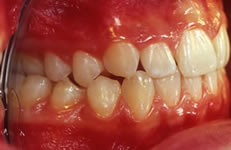

Terapia ortodontica - Prima (FIG 1)

La paziente S.A., di anni 12, presenta morso crociato posteriore monolaterale (fig. 1) dovuto a deviazione della mandibola verso destra in fase chiusura , pertanto le linee interincisive risultano non coincidenti (fig. 2). Si rileva inoltre l’assenza in arcata del canino superiore di sinistra ( incluso) e carenza di spazio per lo stesso (fig. 3 e 4).